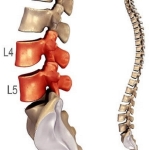

Thoái hóa đốt sống cổ là tình trạng bệnh lý do thoái hóa của các xương, sụn, các cơ dây chằng, các phần mềm và bao hoạt dịch của đốt sống. Bệnh thoái hóa đốt sống cổ thường có các biểu hiện sớm thường gặp là:

Thoái hóa đốt sống cổ là do thoái hóa hệ thống xương cột sống vùng cổ, gây bởi các nguyên nhân khác nhau như chế độ dinh dưỡng, công việc, lao động, hoạt động, tuổi tác. Nó là quá trình gây bệnh ở các đốt sống và xương đốt sống cổ, đầu tiên là sự suy giảm mật độ ở các đốt xương, cộng thêm sự hư khớp ở các thân đốt, đĩa liên đốt tới các màng, dây chằng, hậu quả là tình trạng thoái hóa các đốt sống cổ, thoát vị đĩa đệm cột sống cổ gây đau vùng cổ xuất hiện, nhất là khi hoạt động hoặc tác động vùng cổ. Nói cách khác, đây là bệnh của quá trình lão hóa tự nhiên cùng với sự chăm sóc xương khớp chưa đầy đủ kết hợp với 1 trong các yếu tố thuận lợi tác động. Bởi vậy, bệnh này rất thường gặp ở độ tuổi trung niên, trong khoảng từ 30-50 tuổi.